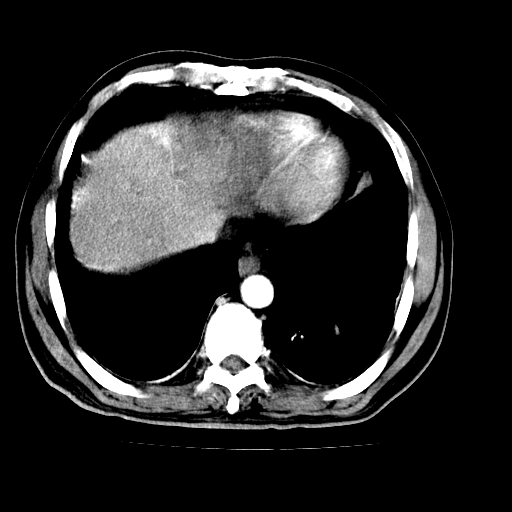

男,66岁,上腹部不适、黄染一周。彩超示:肝左叶占位,肝内胆管扩张,胆总管扩张,胆总管占位?

象胆管细胞癌,但又没有看见明显强化结节,陶瓷胆囊,十二指肠及胆总管显示不清晰,难下定论。

肝左叶不规则软组织肿块影,边缘不规整邻近肝实质受累分界不清;肝内胆管(左叶)明显扩张成“软藤状”,诊断:肝左叶胆管细胞癌。

肝左叶占位性病变,并胆管扩张,符合胆管细胞癌ct表现,门脉左支受累,左肾囊肿。窗宽太窄了,其他的看不清

肝左叶不规则软组织肿块影,边缘不规整邻近肝实质受累分界不清;肝内胆管(左叶)明显扩张成“软藤状”,诊断:肝左叶胆管细胞癌。胆囊钙乳症。